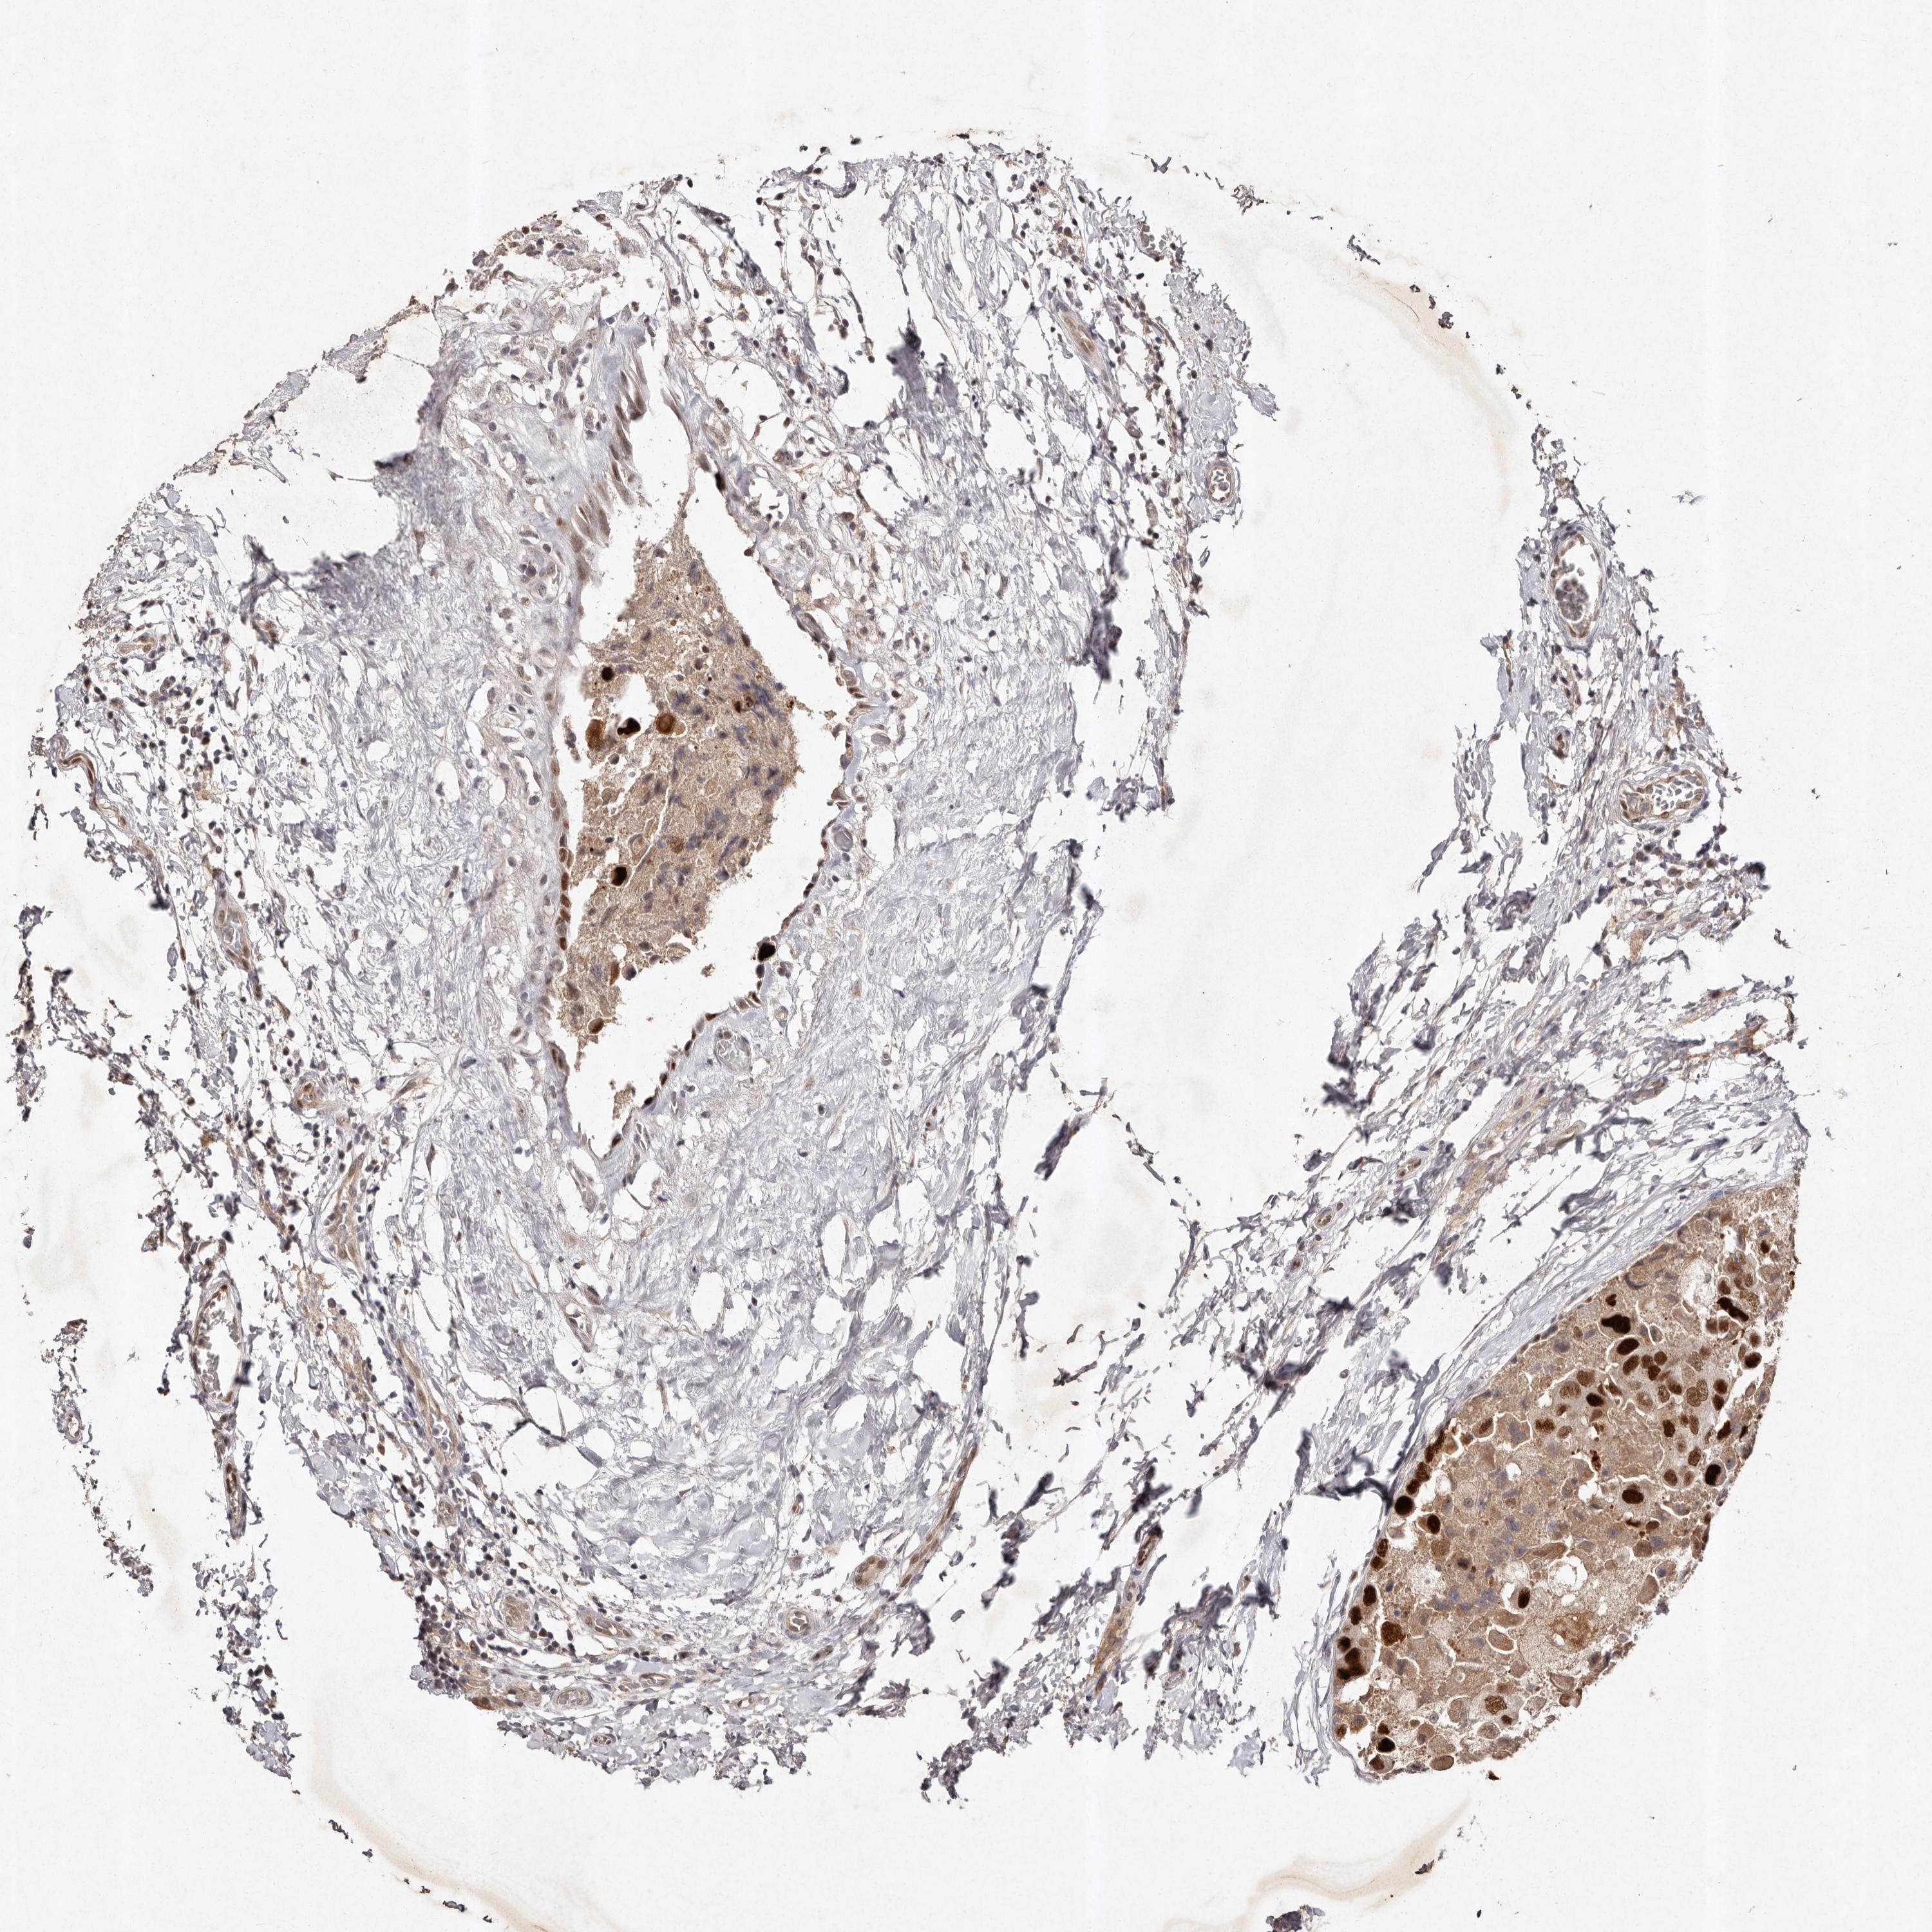

CANCER BREAST CANCER Show tissue menu

BRCA TCGA BRCA VALIDATION PROTEIN EXPRESSION

Breast cancer

Human cancer

Breast invasive carcinoma